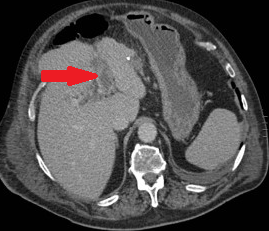

Μεταεγχειρητικό CT. Σαφής μείωση αιματώματος. Χωρίς σημεία απόφραξης εντέρου ή εντερικής ισχαιμίας (Ευγενική παραχώρηση Dr. V. Penopoulos)

Μετεγχειρητική αξονική τομογραφία κοιλίας. Υποχώρηση αιματώματος. Απουσία σημείων εντερικής απόφραξης ή ισχαιμίας (Ευγενική παραχώρηση Dr. V. Penopoulos)